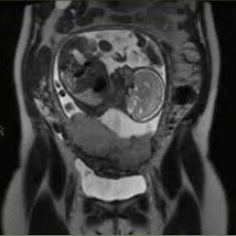

Resonancia nuclear magnetica obstetrica.883442 Idime. (2022)

Bogotá, Bucaramanga, Cali, Cucuta, Ibagué, Pereira |

$350000 |

IDIME. Instituto de Diagnóstico Médico. Código de Convenio : 8915